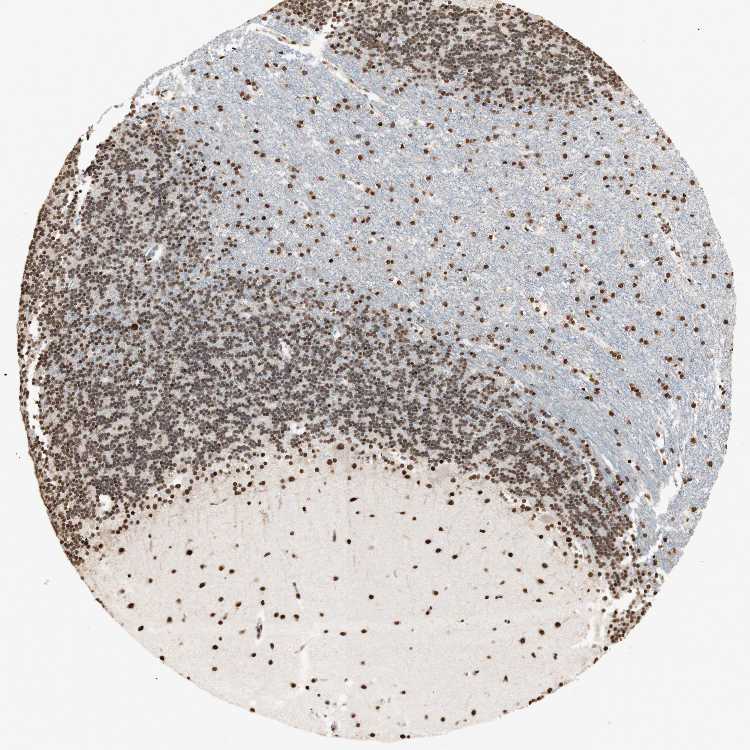

BRAIN CEREBELLUM Show tissue menu

CEREBELLUM - Expression summary

Cells in granular layer: Medium

Cells in molecular layer: High

Purkinje cells: Medium

CEREBELLUM - Antibody stainingi

Antibody staining in the annotated cell types in the current human tissue is reported as not detected, low, medium, or high, based on conventional immunohistochemistry profiling in selected tissues. This score is based on the combination of the staining intensity and fraction of stained cells.

Each image is clickable and will lead to virtual microscopy that enables deeper exploration of all samples and also displays staining intensity scores, fraction scores and subcellular localization as well as patient and tissue information for each sample.

Antibody HPA001666Antibody CAB012403

Purkinje cells HighMedium

Cells in granular layer HighMedium

Cells in molecular layer HighHigh